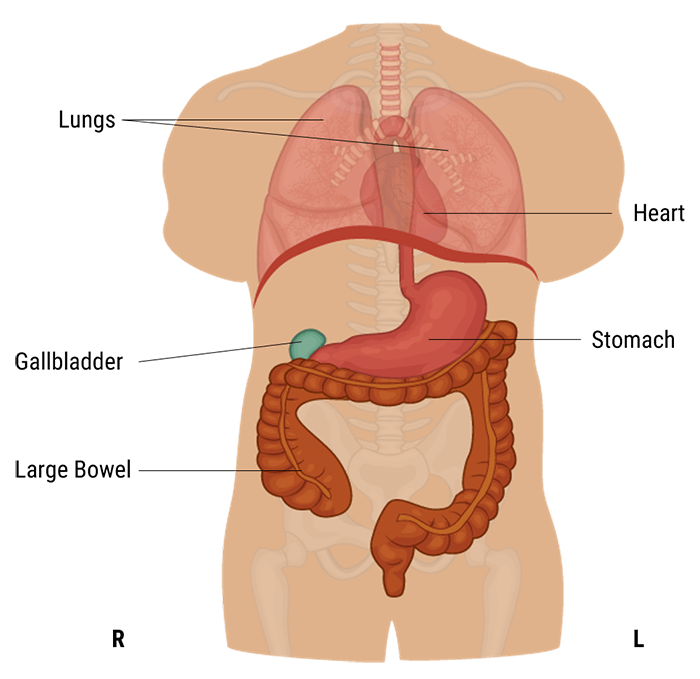

First, we shall know where is located the abdominal and pelvic cavity. The abdominal cavity is a large cavity found in the torso between thoracic pelvic cavities. It is separated from the thoracic cavity by the diaphragm.

A protective layer called the peritoneum, which plays a role in supporting organs, immunity, and fat storage, lines the abdominal cavity. As shown in this diagram, there is no overlapping partition between the pelvic and abdominal cavities.

Now let’s talk about the anatomy of the abdominal cavity and have a summary of the function of each organ.

The abdominal cavity is the largest body cavity in humans, it is lined by a thin, serous membrane called the peritoneum and contains different vital organs such as the liver, gallbladder, stomach, spleen, pancreas, kidneys, ureters, intestines, and the arterial and venous systems.

The stomach is a thick-walled digestive organ found on the left side of the abdomen. It is followed by the first portion of the small intestine, called the duodenum.

The Liver is the largest organ in the abdomen. It is located on the upper right side of it, right under the diaphragm. It has two lobes that are separated by a ligament. It plays a crucial role in our bodies as it maintains normal blood glucose levels, produces bile, and detoxifies the blood.

The Gall bladder is found below the liver and is connected to it. It stores and concentrates bile that is sent to the duodenum when needed for fat digestion and absorption.

The spleen is part of the immune system. Its functions include taking part in the production of white blood cells, storing platelets, and destroying dead red blood cells and harmful substances.

The Pancreas is a part of the digestive system, it produces important digestive enzymes, as well as insulin and glucagon, which are crucial for the metabolism of carbohydrates in our bodies.

The small intestine is found between the stomach and large intestine and is made up of three parts: the duodenum, jejunum, and ileum. It is a long, tube-shaped digestive organ, where digestion and absorption of nutrients take place.

The large intestine is the organ to which undigested material is sent. It is U-shaped and is made up of the cecum, colon, rectum, canal, and appendix. Absorption of water and electrolytes and the formation of feces all occur here.

The two kidneys are found on either side of the abdomen. They play an essential role in the body, because they ensure the detoxification of the blood, the creation of urine, and the maintenance of water and acid balance in the body. Attached to each kidney are tubes, called the ureters, which connect them to the urinary bladder. In addition to the kidneys’ functions, the adrenal glands found on the kidneys produce important hormones, such as norepinephrine and ADH.

A hypersthenic person is a very muscular, thick-set individual, with a broad bony chest and high diaphragm. In this body type, the stomach tends to lie transversely and the gall-bladder horizontally high in the abdomen, well away from the midline. The transverse colon is also high, as well as the heart and the lungs.

A sthenic person is a muscular, thick-set individual similar to hypersthenic but not quite as broad in relation to height. The stomach and gall-bladder lie more vertically and the transverse colon curves lower.

Whereas, asthenic individuals have a long, thin, and lean chest with the diaphragm, stomach, gall-bladder, and transverse colon situated lower down than hypersthenic and sthenic types. In the erect position, the stomach and transverse colon descend into the pelvis.

Finally, hyposthenic individuals are similar to those of the asthenic type but stomach, intestines, and gallbladder are situated higher in the abdomen. They are characterized by a long, shallow thorax, a long thoracic cavity, a long, narrow abdominal cavity, and a slender build.